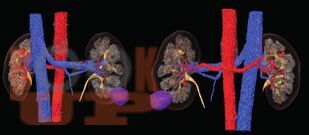

Трехтроакарная лапароскопическая резекция почки

В данном учебном пособии представлены сведения по анатомии и физиологии почек, эпидемиологии, этиологии, патогенезу, клинике, диагностике и современному хирургическому лапароскопическому лечению опухолей почек.